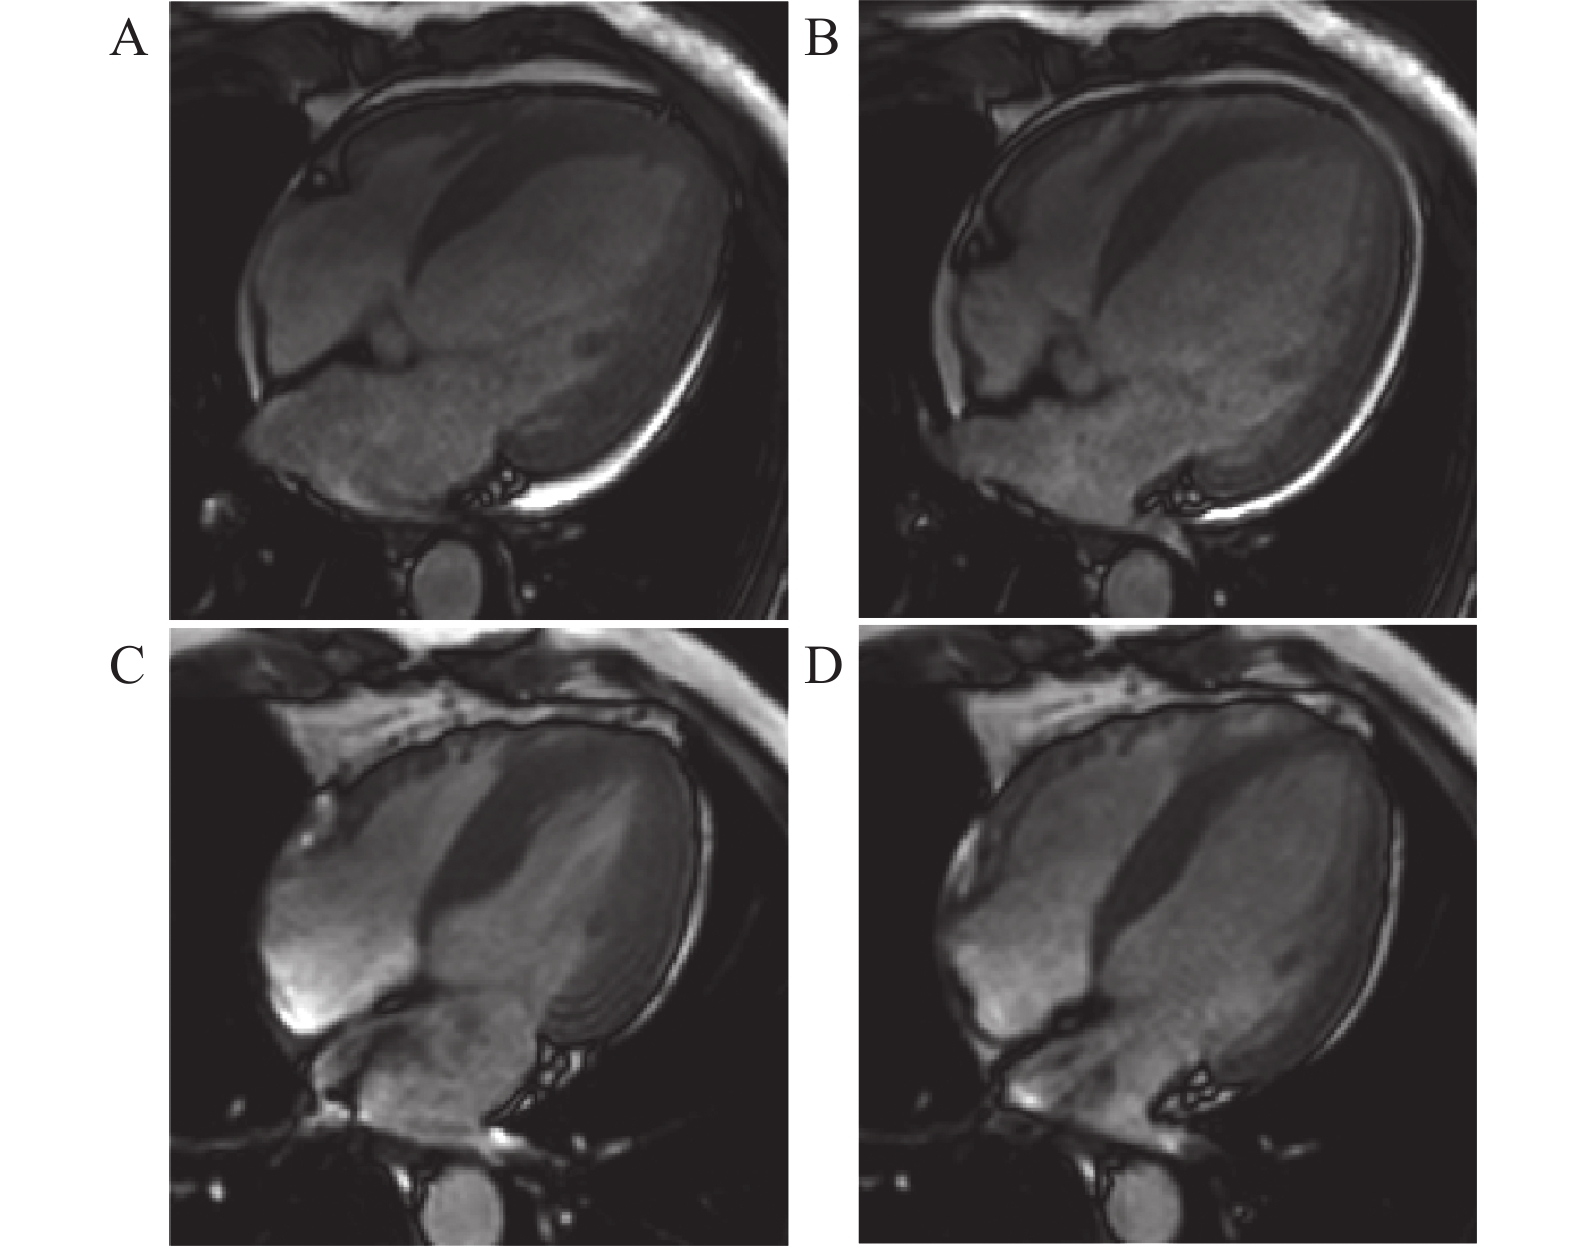

• 图  1  LGE图像后处理

A:短轴LGE序列图像。红线勾画区域为心内膜,绿线勾画区域为心外膜,蓝线勾画区域为正常心肌参考区,黄色区域为延迟强化心肌;B:左室心肌16节段LGE牛眼图。

Figure  1.  LGE Image Post-processing